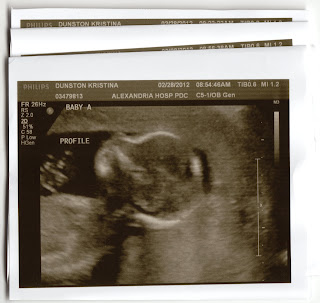

Week 19 and They Are...

Boys! Ryan will be having 2 brothers.

After a lengthy scan today, we found out that both boys are healthy with all of their digits and developing right on track. Baby A currently weighs 10 ounces and Baby B weighs 11 ounces. Mommy will now go back every few weeks to check their growth.